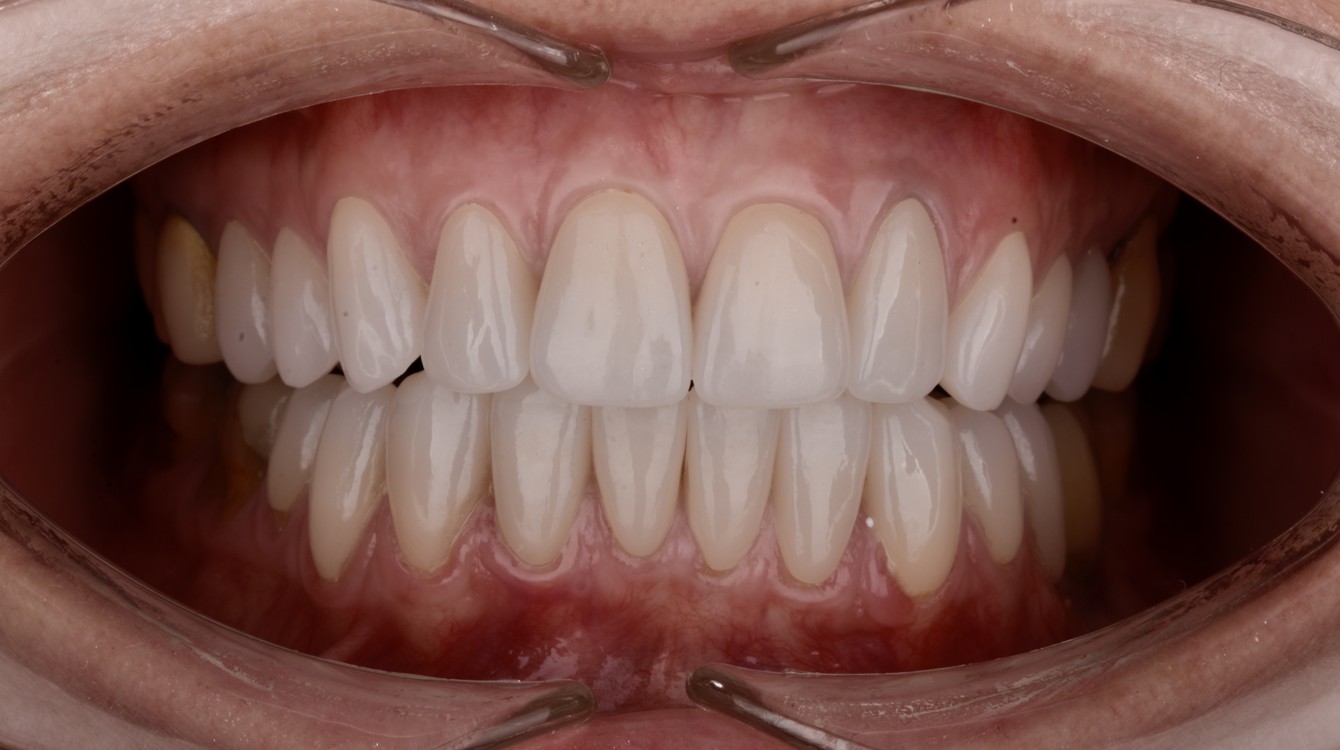

Die Behandlung wurde unter Anwendung computergestützter Planung und der Herstellung eines festsitzenden Zahnersatzes mit CAD/CAM-Technologie durchgeführt. Dadurch wurde gewährleistet, dass die während der Planungsphase festgelegte Form des Zahnersatzes exakt mit dem endgültigen Ergebnis übereinstimmt.

Nach einer umfassenden Untersuchung und Beratung empfahlen wir die Anfertigung von Einzelkronen aus Zirkonoxid sowie die chirurgische Abdeckung der Rezessionen im Unterkiefer. Um den Behandlungsplan für die Patientin möglichst anschaulich darzustellen, wurde ihr neues Lächeln mithilfe des Digital Smile Design (DSD) präzise entworfen.

Romina war aktiv an der Gestaltung ihres idealen Lächelns beteiligt und erhielt die Möglichkeit, das geplante Ergebnis vorab zu betrachten. Die Patientin zeigte sich äußerst zufrieden mit der Präsentation, woraufhin wir mit der Behandlung begannen. Die gesamte Therapie erstreckte sich über einen Zeitraum von drei Monaten.